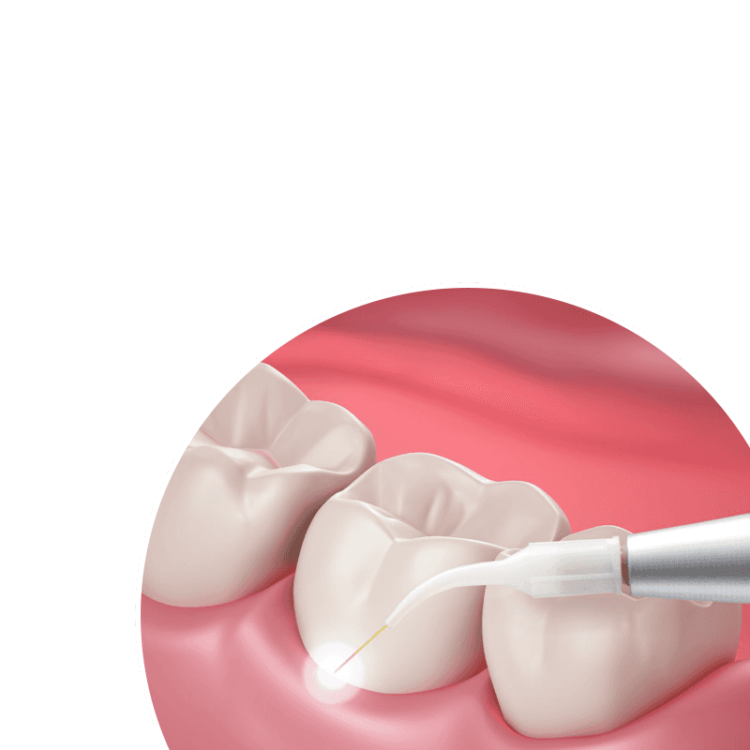

LAPIP is generally performed under local anesthesia and requires one to two appointments of around two hours each. During a typical LAPIP session, your doctor will:

- Use the PerioLase® MVP-7™ laser to vaporize bacteria, diseased tissue, and other debris inside the periodontal pocket.

- Remove contaminants from the surface of the implant using an ultrasonic scaler.

- Gently modify bone tissue, if necessary.

- Reinsert the laser to eliminate any remaining debris and encourage a blood clot to form around the implant.

As you heal, the stem cells from your bone naturally promote tissue regeneration. This encourages your tissue to reattach to the implant post and form a more stable connection.